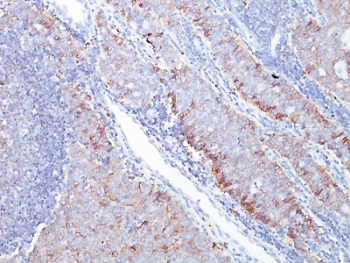

IHC staining of FFPE human ovarian carcinoma tissue with SLC2A1 antibody (clone GLUT1/7308). Inset: PBS used in place of primary Ab (secondary Ab negative control). HIER: boil tissue sections in pH9 10 mM Tris with 1 mM EDTA for 20 min and allow to cool before testing.